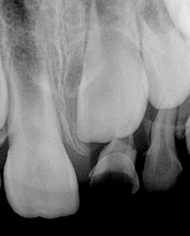

Fase ortopédica: posterior al proceso de cicatrización fueron colocadas dos placas de Hawley con tornillo (8mm) de expansión transversal para realizar una expansión dentoalveolar lenta de 1 mm por semana (2 giros cada tres días) y usadas como mantenedores de espacio para OD 74 y 84, se realizó control clínico y radiográfico mensualmente. Aproximadamente a los 4 meses de evolución se observó la erupción espontánea del órgano dental 21 (Figura 3).

A. Colocación de placas de Hawley en maxilar superior e inferior, B. Evolución a los 4 meses, se observa erupción espontánea del OD 21.